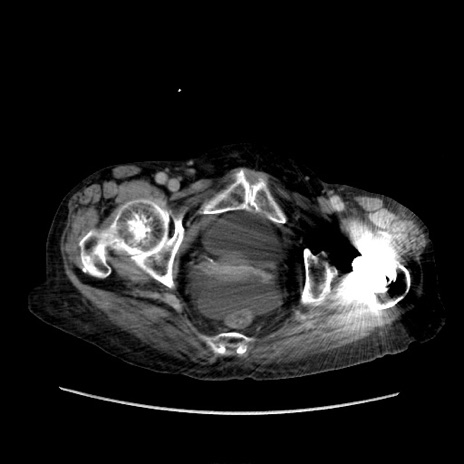

症例31(横断像)

【症例】80歳代 女性

【主訴】腹部膨満感

【現病歴】他院にて肝硬変にてフォロー中。1週間前から便秘、腹部膨満感、臍部腫瘤あり受診となる。

【既往歴】肝硬変

【身体所見】腹部膨隆あり、皮膚変化なし、疼痛なし。

【データ】WBC 4600、CRP 0.25